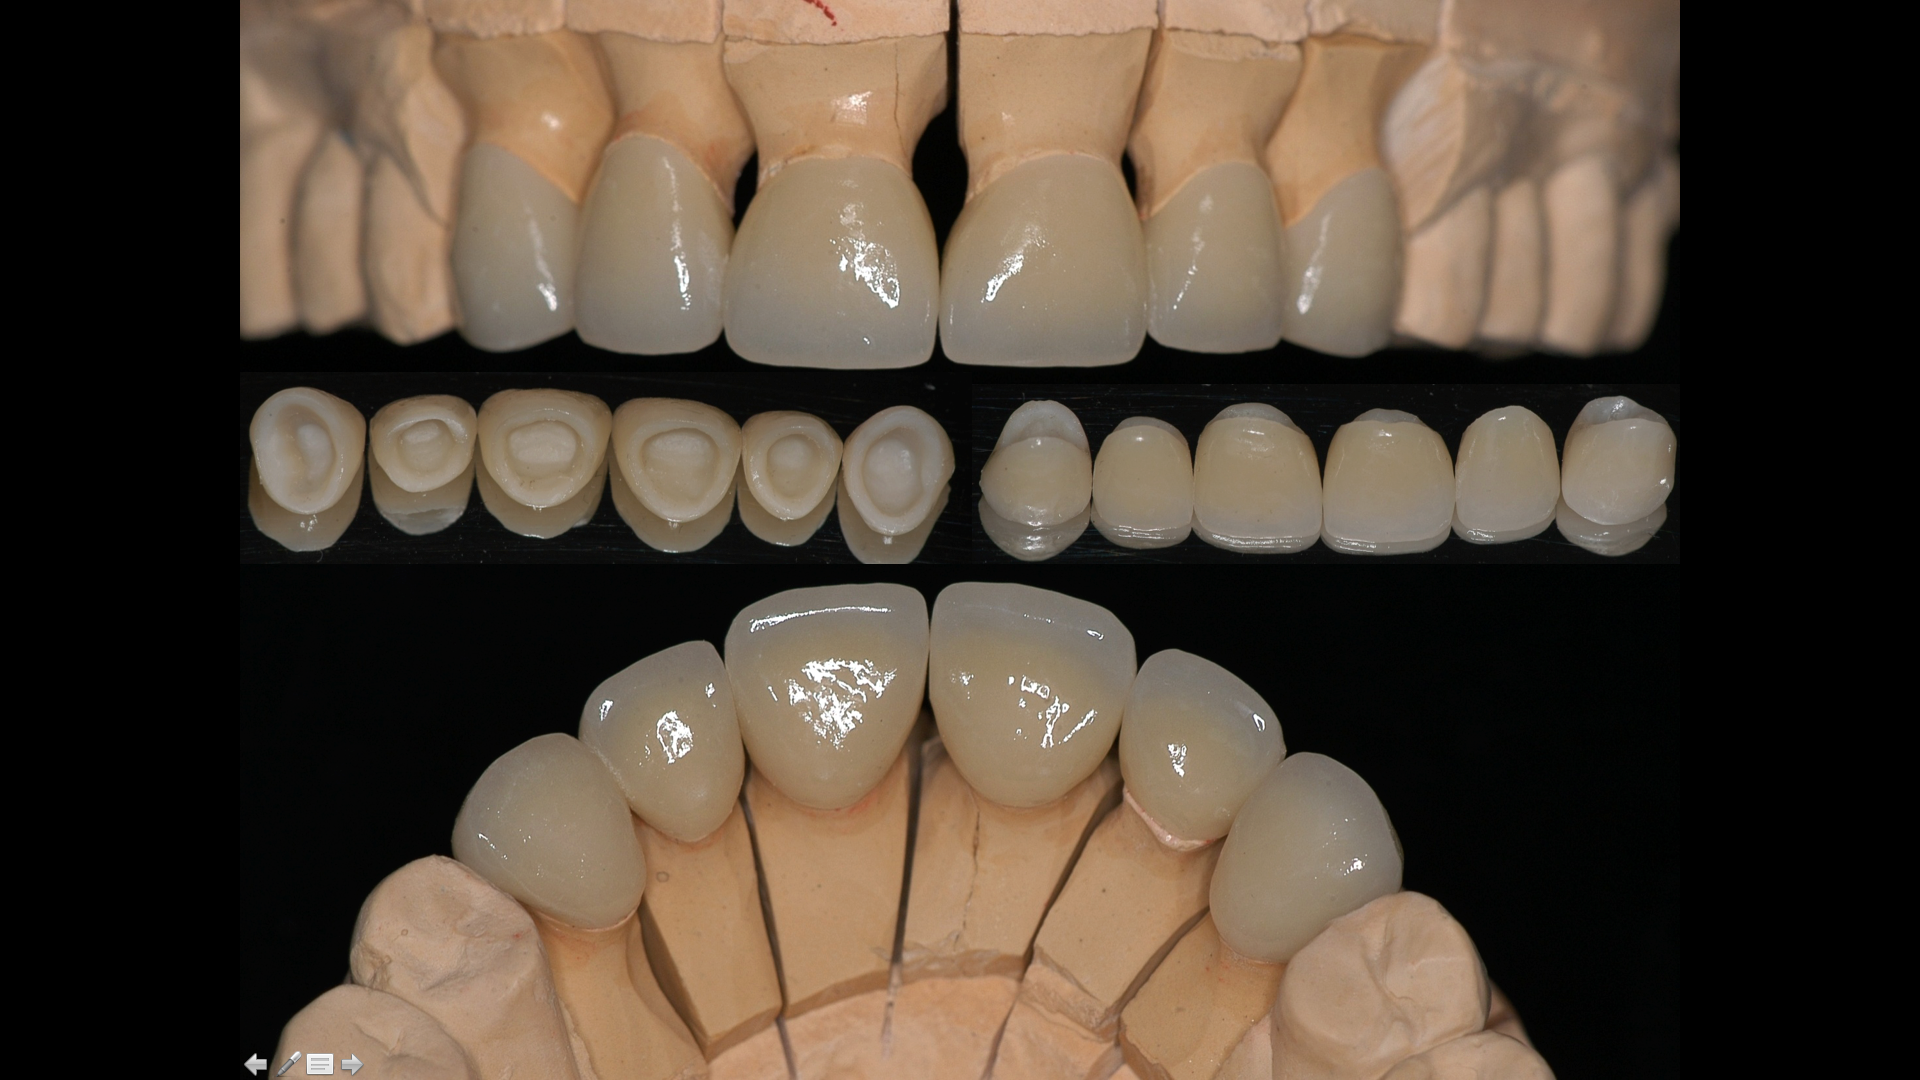

The management of the anterior open bite may be quite challenging and in some cases necessitates a multidisciplinary approach. We present here a patient suffering from an anterior open bite with an ankylosed central incisor due to previous trauma. The anterior open bite was corrected using conventional orthodontics and the ankylosed incisor was repositioned in the correct tri dimensional position using segmental osteotomy. The repositioned bone block needed 5 months of stabilization and the prosthetic rehabilitation of the anterior maxilla was completed using e-max crowns. At 24 months ,the result was stable with no relapse and an excellent pink and white esthetic score.